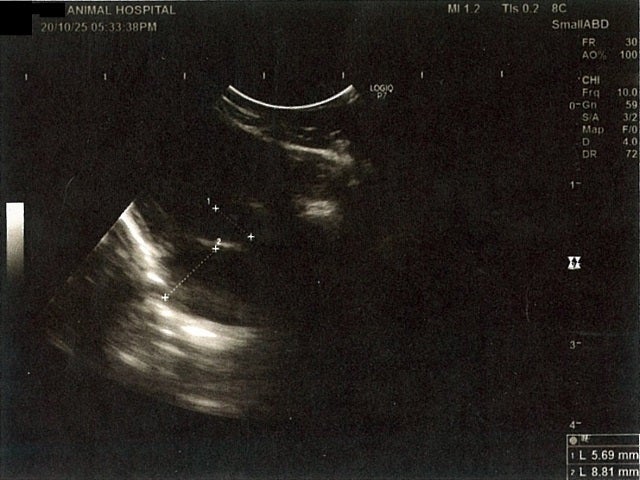

《心臓周りの胸部以外の全ての腹部で腹水がみられるとの診断です》

大網という部分で内臓を包む膜のようなものです。その周りに腹水が溜まっています。

膀胱周りに腹水が確認できるエコー写真

膵臓周りに腹水が確認できるエコー写真

肝臓周りに腹水が確認できるエコー写真

心臓のみ腹水が確認できないエコー写真